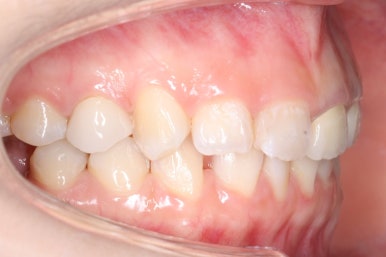

초진 때의 입안 모습입니다.

앞니는 고른 편이였으나 군데군데 틈새가 있었습니다. 약간 삐뚠 모습도 보이지만 환자분께서 개선을 하고자 했던 부분은 아래쪽 어금니 1개가 없는 자리였습니다.

부산부분교정 키다리아저씨치과에 처음 내원하셨을 때의 얼굴 모습입니다.

치아가 약간 삐뚤어져 있는 모습을 보이긴 하지만 환자분 스스로 개선을 할 필요성을 느끼지 못하셨고 적극적으로 개선을 해야 할 만큼의 얼굴 모습이 아니기에 어금니만 하기로 한 것이죠.